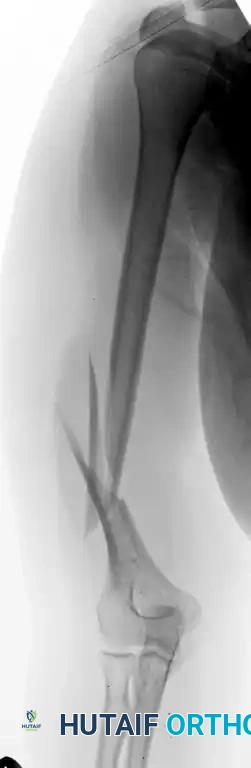

Figure 57-39 A: Fracture of the distal third of the humeral shaft.

Figure 57-39 B: Postoperative radiograph after plate fixation through a posterior triceps-splitting approach.